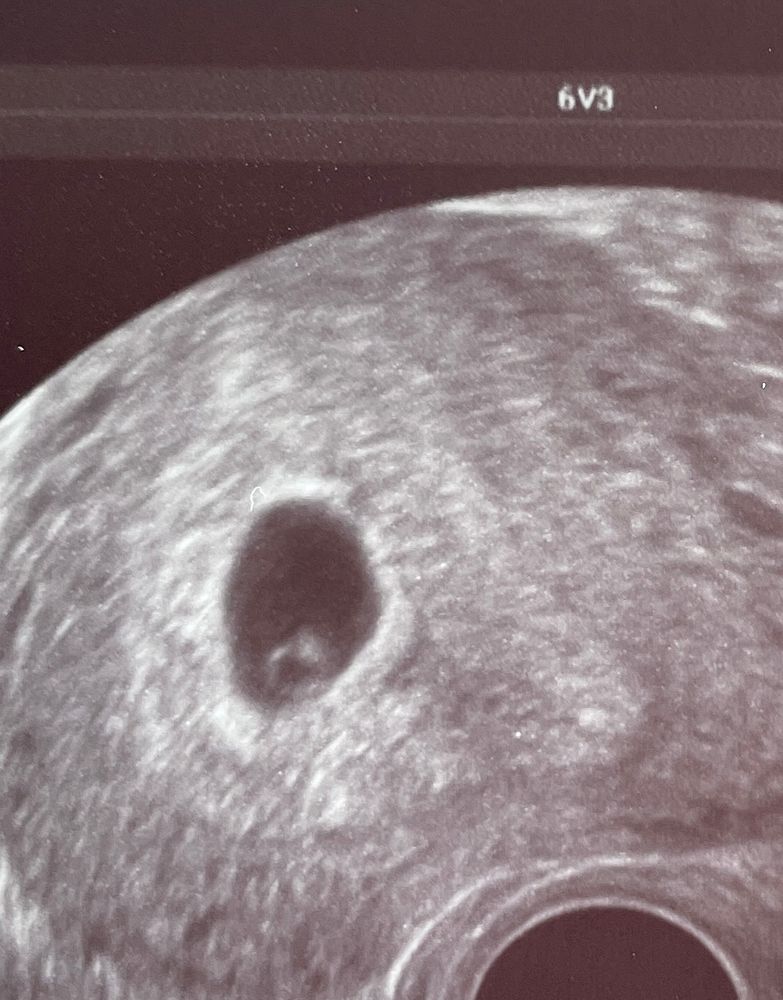

Колечко с камнем было на 6.2 акушерской неделе) на 5.2 было только круглое плодное яйцо Изображение

Дарина, ой, какое красивое колечко 😀👍🏻 Тоже хочу такое застать. Это получается ЖМ с эмбрионом? Сердцебиение уже было?

Лиана, спасибо 😄 да, всё уже было)